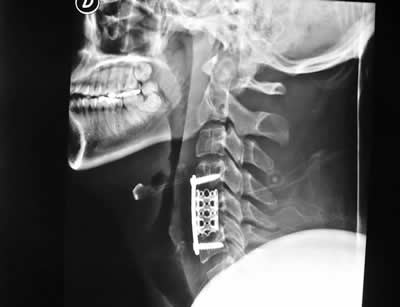

IMÁGENES

Galería de imágenes